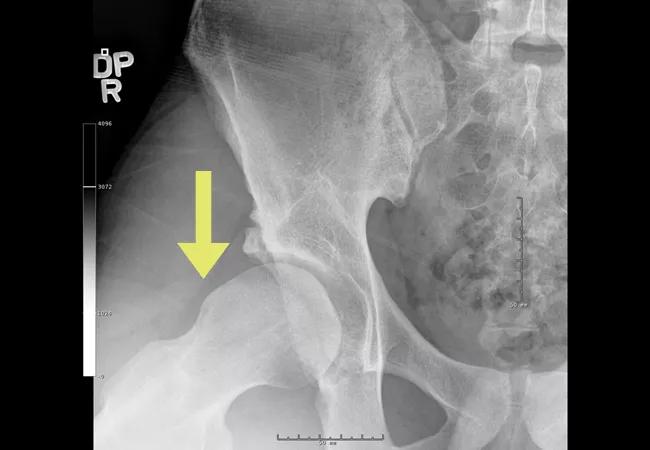

17-ORT-1044 Rosneck ConsultQD_Inset 1_

AP radiograph of the pelvis shows the os acetabula (blue arrow) as part of impingement pattern